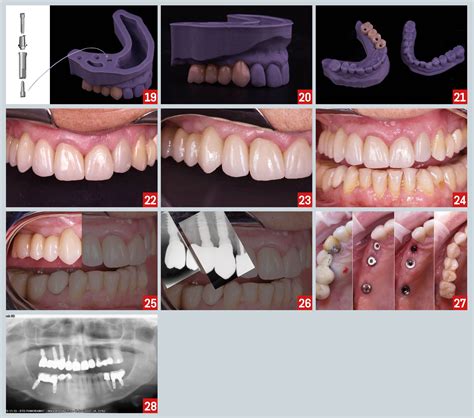

A 3 unit dental bridge is a specialized dental appliance used to replace a single missing tooth. The term "3 unit" refers to the total number of components involved in the structure: two dental crowns—known as abutments—that are placed over the healthy teeth adjacent to the gap, and one artificial tooth—known as a pontic—that fills the space in between.

By anchoring the prosthetic to the neighboring teeth, the 3 unit dental bridge creates a sturdy, permanent fixture that allows you to bite and chew with confidence. It is a highly popular choice for patients who may not be candidates for dental implants or who prefer a non-surgical approach to tooth replacement.

During the first visit, your dentist will prepare the two healthy teeth on either side of the gap. This involves removing a small amount of enamel to make room for the crowns that will eventually anchor the bridge. Once the teeth are shaped, the dentist will take precise impressions of your teeth, which are sent to a dental laboratory to create your custom bridge.

At your second appointment, your dentist will remove the temporary bridge and test the fit of your permanent 3 unit dental bridge. They will check the color match, the bite alignment, and ensure the bridge feels comfortable. Once everything is confirmed, the bridge is permanently cemented or bonded into place.